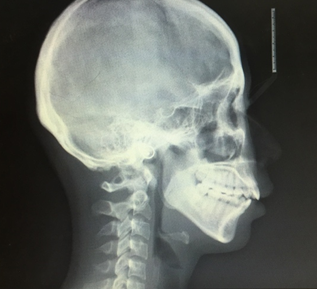

因为我已经拍过xray确认过我牙齿的健康情况了,所以就跳过了这一步,不过也可以附上之前在其他诊所拍的图,供大家欣赏。

大晚上看这种图可能不太好,但是也可以看出来我是明显的开咬合和过咬合。